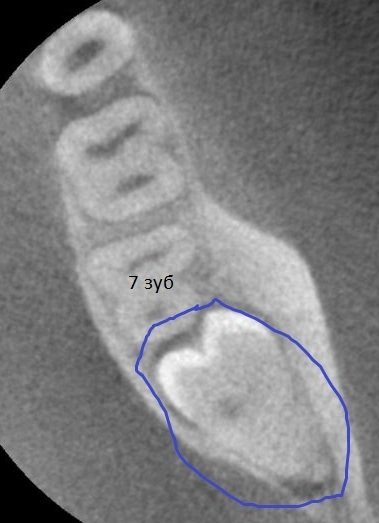

На протяжении трёх дней беспокоила несильная ноющая боль с правой стороны внизу. Сделали снимок, врач предположил, что боль возникает из-за зуба мудрости, который ещё не прорезался. И сразу записала на удаление.

Однозначно, причина беспокойств — это неправильно расположенная восьмёрка. Удаление необходимо, в противном случае мы получим скученность всего зубного ряда и потеряем седьмой зуб. Удаление сложное и требует профессионализма и опыта. Потребуется моя помощь — запишитесь к нам на приём к челюстно-лицевому хирургу.